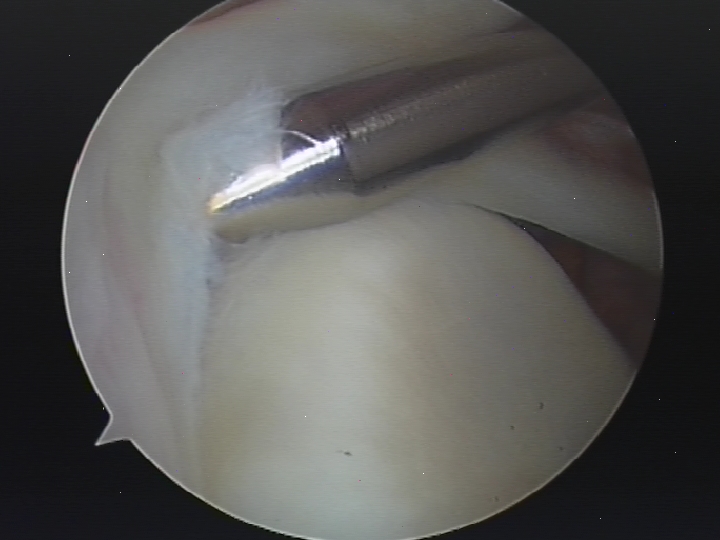

- Arthroscopic (key hole) surgery is the surgical treatment of choice in patients with symptomatic SLAP injuries. About 2-3 incisions of ½ cm to 1 cm are needed and a telescope is passed into the shoulder through one of these incisions. Special surgical instruments are passed through the other incisions. The injury is initially assessed and graded. There are 4 grades described and further treatment of the injury depends on the grade of injury. The advantage of keyhole surgery is that it is less traumatic and so recovery is quicker. It is usually carried out as a day procedure. Loss of movement of the shoulder is rare after arthroscopic repair. Debridement of the SLAP tear: If the tear is a small and at the edge of the labrum, the loose portion of the labrum is trimmed to a smooth edge. Arthroscopic repair of the SLAP tear: With this surgery, the upper part of the labrum is repaired and reattached to the bone by using special suture anchors. This type of surgery is practiced for tears that are unstable. Arthroscopic tenodesis of the biceps tendon: With this surgery, the tendon attached to the upper part of the labrum is cut and reattached to the upper humerus. The principle behind this surgery is that the tendon will not pull on the torn labrum and the symptoms will improve. This surgery is practiced in degenerative, unstable SLAP injuries.

Arthroscopic repair of SLAP tear.